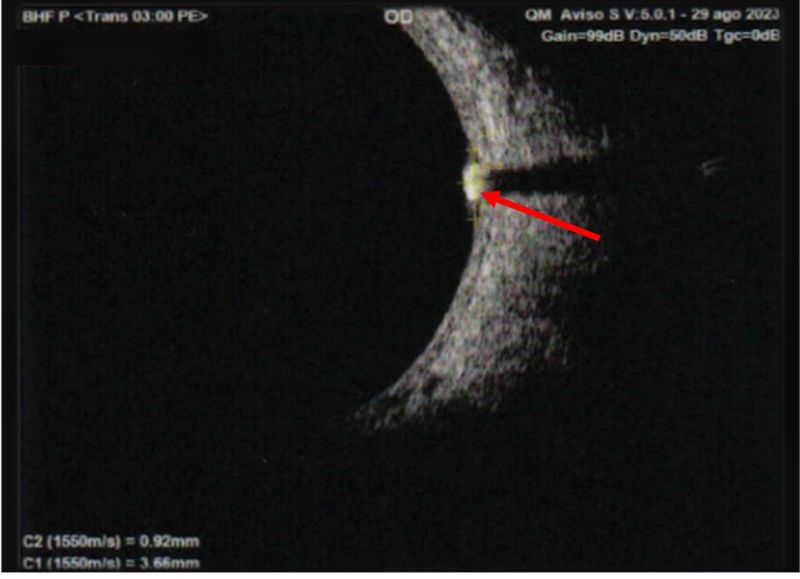

Figure 3: B-scan ultrasound OD: a subretinal lesion is observed in quadrant M3, measuring 3.28 × 3.66 mm at the base and 0.92 mm in height, with internal calcification and posterior attenuation. Findings are suggestive of an astrocytic hamartoma.